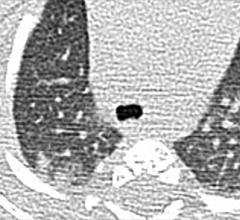

Computed tomography (CT) systems use a series of X-ray images to create an image volume dataset with slices that can be manipulated on any plane using advanced visualization software. The section includes computed tomography scanners, CT contrast agents, CT angiography (CTA and CCTA), CT perfusion, spectral CT (dual-source CT), and iterative reconstruction dose reduction software.

May 21, 2020 — RADLogics announced that its AI-powered medical imaging applications designed to assist in the detection ...

April 21, 2020 — RADLogics announced new worldwide deployments and installations of the company’s AI-powered solution to ...